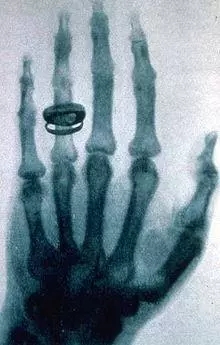

【世界上第一张X光片】

发现X射线后,伦琴用这种射线拍摄了他夫人的左手的照片,显示出手的骨骼结构,从而才有了这张世界上第一张X光片。据说那枚戒指是他们的订婚戒指。

图为当年伦琴妻子左手的X光照射图